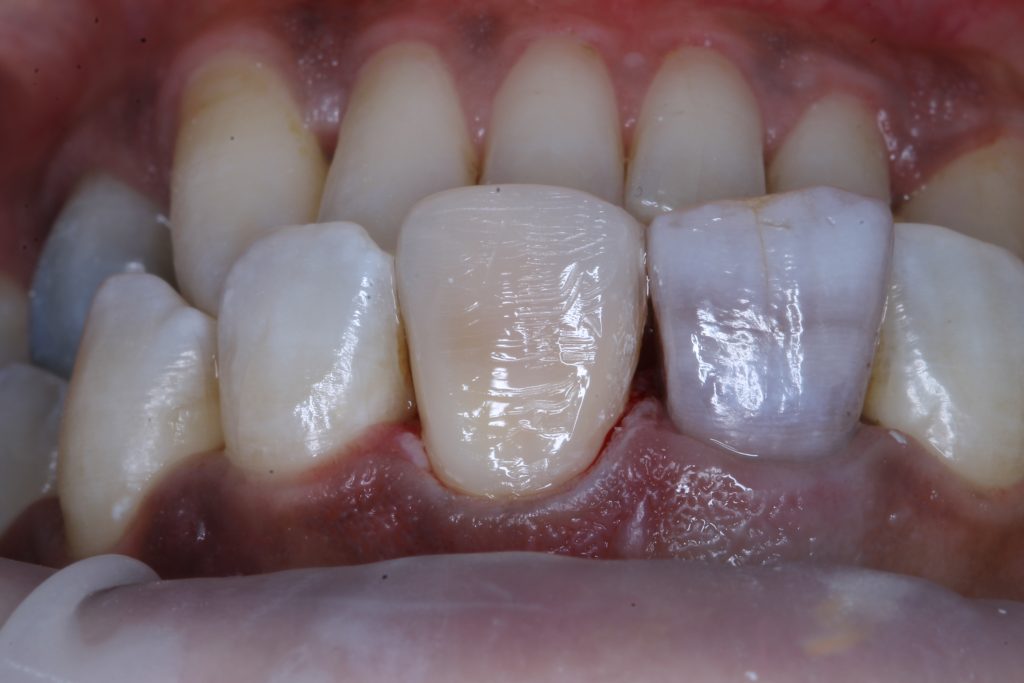

in the next visit internal bleaching applied for one week

final composite filling.

Discoloration of the affected tooth

After one week of internal bleaching